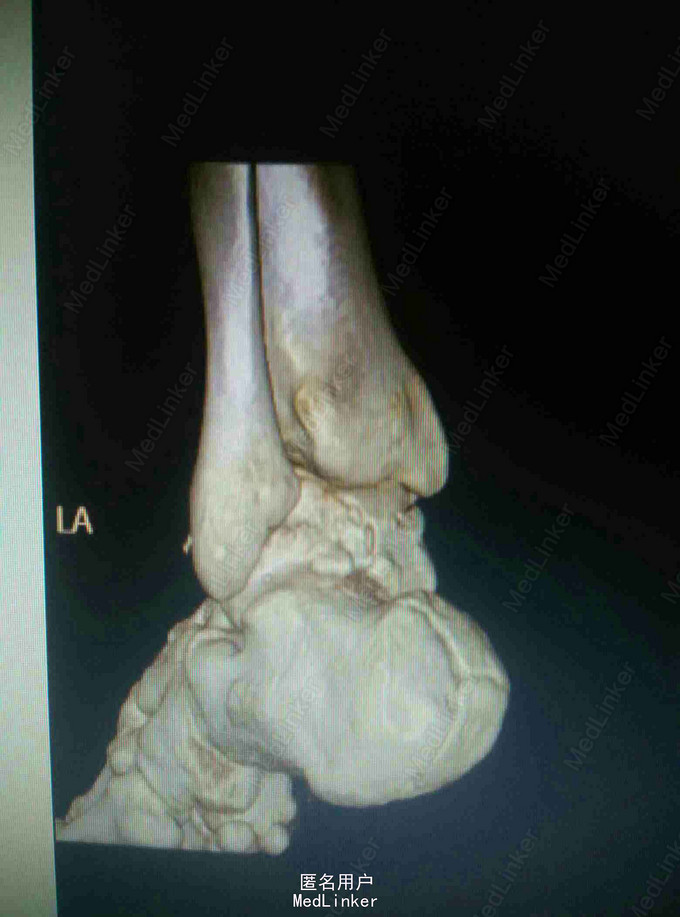

距骨骨折采用外踝截骨入路显露固定手术

患者,男,27岁,高处坠落致左踝部肿痛,活动受限

完善X线片及CT扫描检查